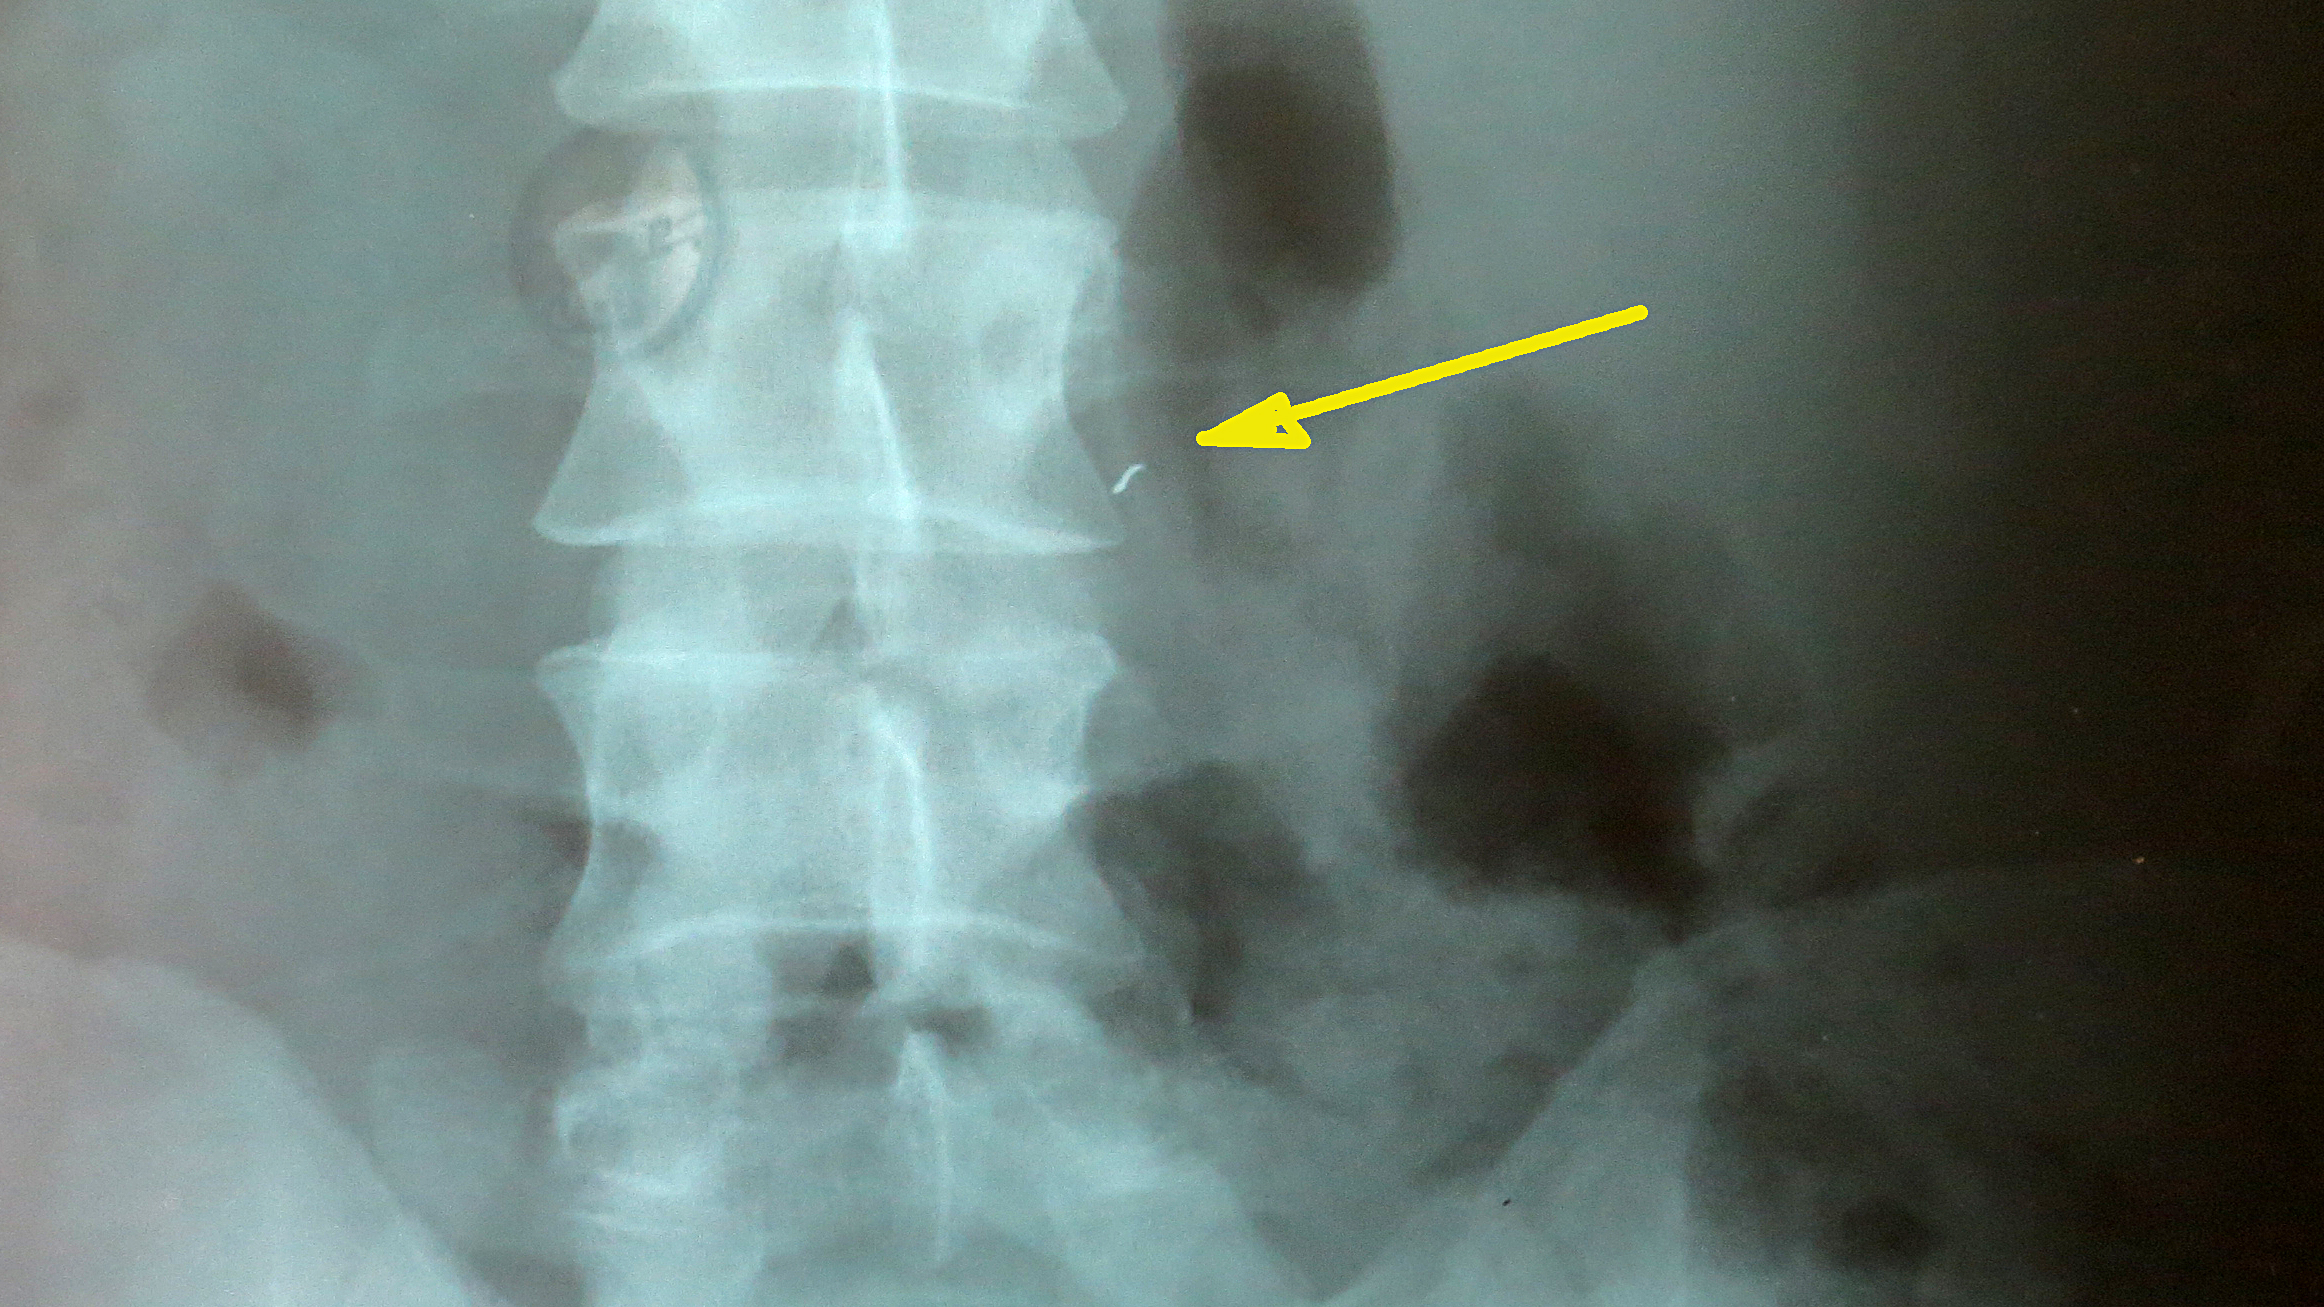

В результате взрыва гранаты за спинами милиционеров, в Сергея попало три осколка. Защитил бронежилет и шлем. Без них поражений было бы гораздо больше. А так осколки попали только в незащищенные места: поражены рука, нога и спина (осколок вошел ниже бронежилета).

– Насколько быстро мне оказали медицинскую помощь – сказать не могу, там, как-то планка времени теряется. Меня, и еще 10-15 человек, вывозили на военном автобусе. Я так понял, что это был автобус Нацгвардии. Обезболивающее еще на месте взрыва мне уколол кто-то из медперсонала военных. А в госпитале к нам сразу же вышел врач, осмотрел всех, кого привезли. Тяжелораненых сразу забрали на операцию – никто ничего не ждал. Медики работали очень оперативно. А нас уже распределили по степени тяжести. Потом: рентген, хирургия – и по палатам, – вспоминает Сергей.

– «Тяжелых» у нас нет. У всех – осколочные ранения. Сейчас в нашем отделении осталось пять человек. Еще есть раненые в нейрохирургии. Пока с осколками ничего делать нельзя. В первый период после травмы всегда есть оттек, есть воспаление. С этим мы боремся: перевязки, антибиотики. Для лечения все есть. По поводу осколков: достать его через входное отверстие практически невозможно. А он засел в массе мышц. Для того чтобы достать осколок, нужно делать большой разрез и «рыться» между мышцами. А этого, мы считаем, делать не следует. Зачастую сама операция более травматична, нежели наличие мелкого осколка. Природа устроила все так, что организм хочет «закрыть» очаг воспаления. Поэтому осколок со временем «капсулируется» – обрастает рубцовой тканью. Если не задеты ни сосуды, ни нервы, то это – не показание к операции, – разъясняет ситуацию и.о. заведующего отделением травматологии Михаил Швец. – Вообще-то, осколки могут и сами выйти. Но в данном случае осколки не круглые, а сложной формы и вряд ли выйдут самостоятельно. Но с такими осколками, полученными еще во время войны, люди и до сих пор живут.